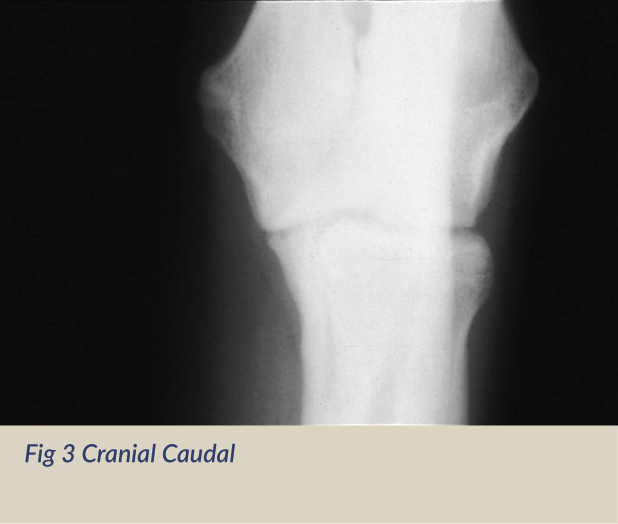

The International Elbow Working Group (IEWG), a consortium of experts from around the world was founded in 1989 to lower the incidence of elbow dysplasia by coordinating worldwide efforts. The diagnosis of elbow dysplasia is based on the presence of degenerative joint disease/osteoarthritis which results from an ununited anconeal process, osteochondrosis or a fragmented medial coronoid process. The OFA started its elbow database in 1990 using a modified protocol of the IEWG. For cost effectiveness and mass screening, the OFA requires the extreme flexed medial to lateral view (Fig 1) of each elbow. Inclusion of additional views such as the neutral medial to lateral (Fig 2), cranial caudal (Fig 3) or preferably the cranial caudal 10-15 degree lateral to medial oblique (Fig 4) can also be submitted and will be evaluated.

In instances where the owner is requesting a re-evaluation of the elbows or if the dog is experiencing lameness it is recommended that the cranial caudal 10 to 15 degree lateral to medial oblique view accompany the required extreme flexed medial-lateral view.